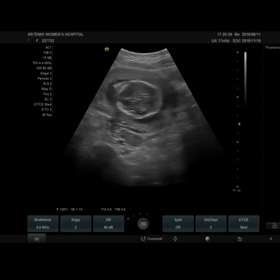

妊婦検診 13w0d 初の3D、4D動画